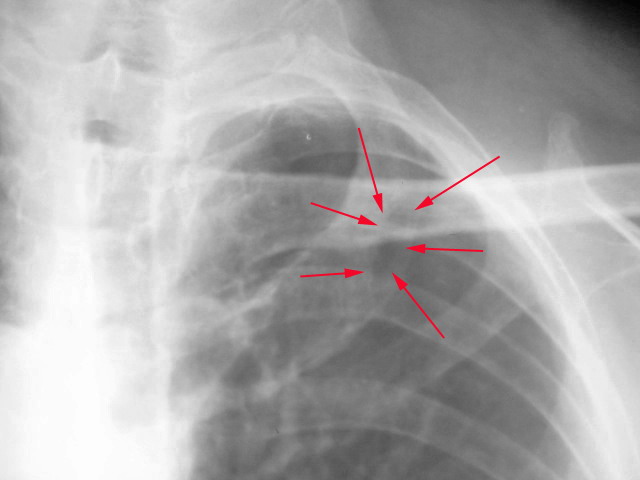

标题: X7541:肋骨透光区

男.55.体检.请问是正常变异吗?

右侧肋骨好象也有,右能是重叠后形成的、

减刹现象。

发育问题。